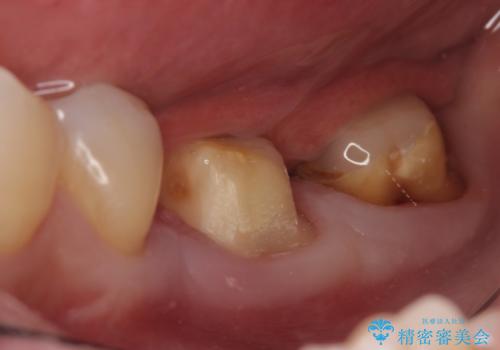

検査の結果左下7は失活(歯の神経が死んでいること)しておりX線上で根尖病変を認めたため、根管治療を行いました。

また左下6は遠心にあった歯茎より深い虫歯(縁下カリエス)の問題を解決するため、歯茎を下げる歯周外科手術を行いました。

歯周外科手術終了後、歯茎の回復を待ち左下6、7ともにオールセラミッククラウン(スタンダード)による補綴を行いました。